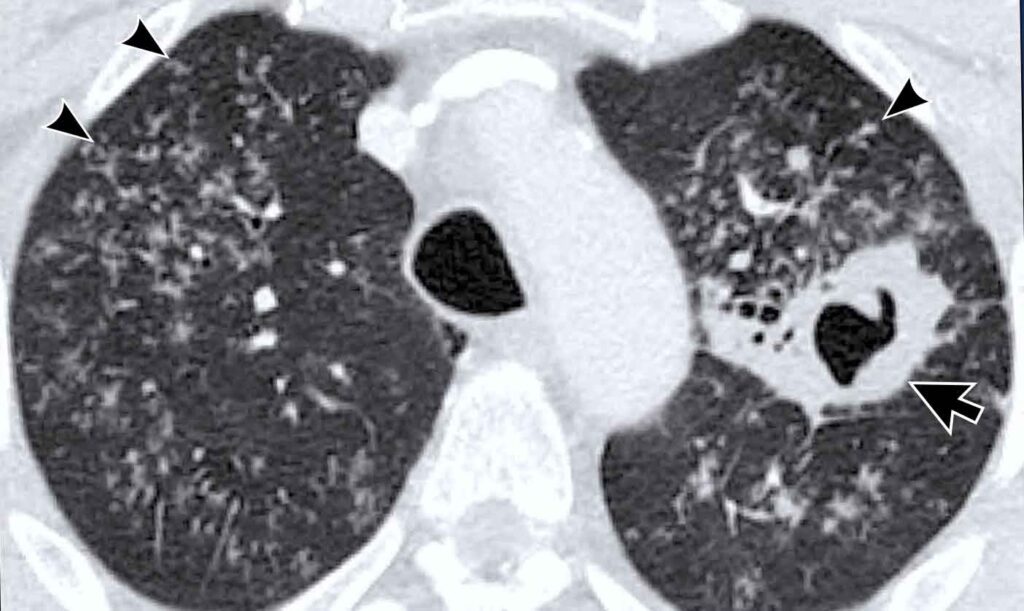

CT-scanning: Et Kvantumspring i Detaljegrad

En standard CT-scanning af brystkassen er markant overlegen i forhold til et almindeligt røntgenbillede. Ved at tage en række tværsnitsbilleder skaber CT-scanneren en detaljeret 3D-model af lungerne. Dette giver radiologer mulighed for at se langt mindre og mere subtile forandringer, som et røntgenbillede ville overse. Studier har konsekvent vist, at CT-scanninger kan identificere yderligere tilfælde af latent TB hos personer, hvis røntgenbilleder blev anset for at være normale. CT kan afsløre små knuder (noduli), fortykkede lymfeknuder og fine arvævsdannelser, som er klassiske tegn på en indkapslet, latent infektion.

Forskere begyndte derfor at undersøge, om LDCT også kunne bruges til at opspore tuberkulose. Den foreløbige forskning er yderst lovende. Selvom der stadig er et begrænset antal store, højkvalitetsstudier, tyder de eksisterende resultater på, at lavdosis CT-scanning kan være et effektivt alternativ til standard-dosis CT for detektion af latent TB. Den er i stand til at identificere de samme subtile tegn på latent infektion, men med en betydeligt lavere strålebelastning for patienten.